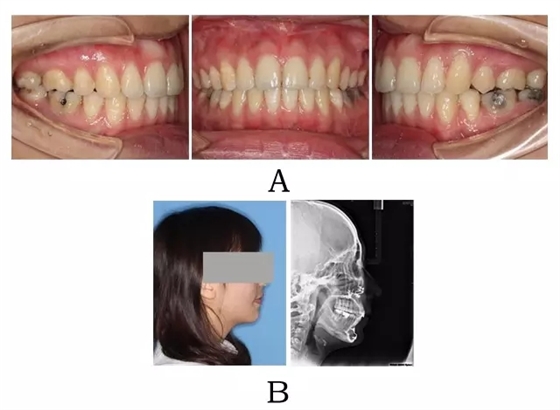

面下部前突,上頜前突、下頜后縮,唇態(tài)往往呈閉合不全。上頜前部齒槽前突,根形不明顯,整個(gè)牙槽肥大,肉眼觀察骨粘膜張力大。上前牙呈直立(骨源 I 型)或內(nèi)傾(骨源 II 型),上下前牙覆合覆蓋在正常范圍。頭顱側(cè)位片往往顯示下頜骨體部呈“三角形”,頦部向下旋轉(zhuǎn),常表現(xiàn)為高角(下頜后縮)(圖2-1)。

圖2-1:骨源性突面畸形臨床表現(xiàn)及頭顱側(cè)位影像特征。

(A)齒槽與牙列特點(diǎn) (B)側(cè)貌與影像對(duì)比

Figure 2-1. Clinical manifestation and cephalometric image for alveolar prognathism. (A) Alveolar and dentition specifics. (B) Facial profile and radiographic image.